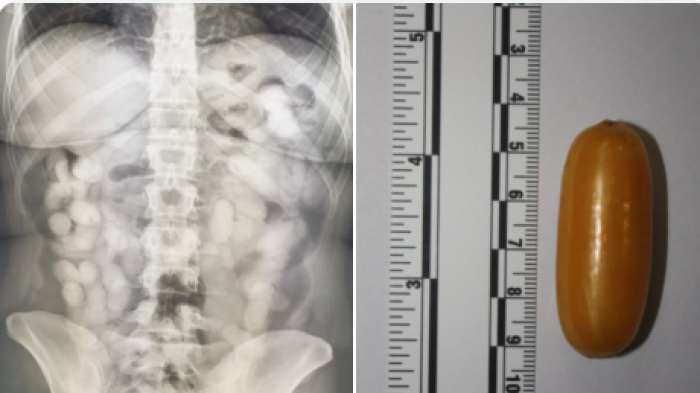

Бразилка фатена на аеродромот во Загреб, со речиси еден килограм кокаин во нејзиното тело | ФОТО

Бразилка била фатена на аеродромот во Загреб „Фрањо Туѓман“ со речиси еден килограм кокаин во нејзиното тело, пренесува „Дневник.хр“.

Таа проголтала 74 капсули кои содржеле вкупно 990 грама кокаин, а биле откриени од членовите на граничната царинска испостава.